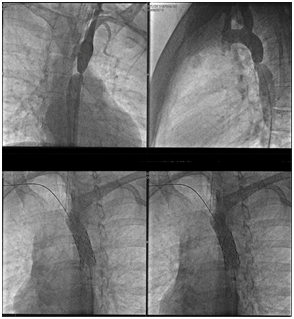

In 2015, she decided to seek a second medical opinion. At this visit, she had absence of lower limbs pulse, shortness of breath on exertion (NYHA II), lower limbs edema and uncontrolled blood pressure. Echocardiogram showed an elevated aortic gradient of 70mmHg, and an AngioCT demonstrated unequivocally an aortic coarctation after the emergence of left subclavian artery. She then underwent a cineangiocoronariography for anatomy assessment. The diameters were 6 and 14mm for the coarcted and descending aorta, respectively (Figure 1).

Figure 1 Cardiac catheterization during procedure and results.

She decided to undergo a balloon angioplasty, motivated by the perspective of a shorter hospitalization time and better recovery. She underwent the procedure in September 2015 with the insertion of an endoprosthesis (Figure 1). After the procedure, she remained hospitalized for 1 day and resting for 5days after discharge. After 10 days, she was able to work and, after 3weeks, she was fully recovered and able to exert physical activity. Her blood pressure was controlled with Atenolol 50mg/day for 3months and she took Aspirin 100mg/day for 6months following the procedure. After one-year, she underwent an angio CT, which showed adequate function of the endoprosthesis, and an echocardiogram which showed normal cardiac function, an adequate aortic gradient of 12mmHg and no valvar nor myocardial abnormalities.